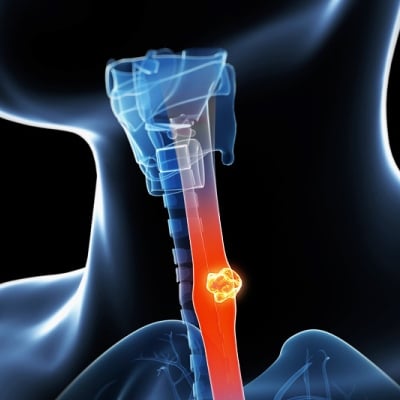

Τα σημάδια θανάτου από καρκίνο του οισοφάγου περιλαμβάνουν μεγαλύτερη δυσκολία στην κατάποση ( δυσφαγία ), καθώς και συμπτώματα κοινά σε άλλους τύπους καρκίνου, όπως: κούραση, έναρξη του πόνου, προβλήματα αναπνοής, αλλάζει στη διάθεση και την ευαισθητοποίηση.

Ποια είναι τα πρώτα σημάδια και συμπτώματα του καρκίνου του οισοφάγου;

- Ο καρκίνος του οισοφάγου συνήθως δεν έχει εμφανή σημεία και συμπτώματα. Όταν εμφανίζονται, το πιο κοινό σύμπτωμα είναι η δυσφαγία .

- Το να τρώτε κανονικές μερίδες μεγέθους δαγκώματος μπορεί να σας κάνει να αισθάνεστε σαν να πνιγείτε ή ότι κάτι κολλάει στο λαιμό σας. Η δοκιμή μικρότερων δαγκωμάτων και μαλακότερου φαγητού, καθώς και η κατανάλωση πολλών υγρών, μπορούν να βοηθήσουν για λίγο.

Άλλα πρώιμα σημεία και συμπτώματα μπορεί να περιλαμβάνουν:

Ποια είναι τα σημεία και τα συμπτώματα του τελικού σταδίου (στάδιο IV) του καρκίνου του οισοφάγου

- Τα συμπτώματα του οισοφάγου τείνουν να επιδεινωθούν καθώς η ασθένεια εξελίσσεται και ο καρκίνος μεταστάσεις. Η δυσφαγία, για παράδειγμα, μπορεί να φτάσει σε σημείο που απαιτείται διατροφή μόνο για υγρά.

Άλλα σημεία και συμπτώματα τελικού σταδίου του καρκίνου του οισοφάγου μπορεί να περιλαμβάνουν: